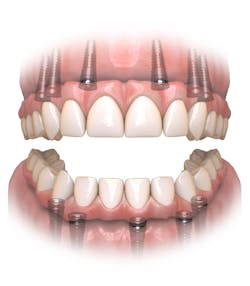

As a prosthodontist who has spent the last 25 years offering full-arch treatment to my patients and teaching the Hybridge full-arch protocols for most of that time, the phrase “Pick a Path” has come to refer to the difficult decision a patient makes to either commit to restoring their natural dentition or to replace their remaining teeth with a completely implant-supported prosthesis, as in a full-arch solution. The last decade has seen this implant modality gain in popularity.

Treatment objectives: Restore or replace all teeth to achieve full function and a natural, healthy-looking smile with a solution that is fixed and will last over the long term (20-plus years).

Today, more than ever, patients expect and hope their dental restoration will solve what has historically been a lifetime cycle of dental problems and expense. In this case, a straightforward, conventional restorative treatment plan that focuses on restoring the patient’s natural teeth may not make the most sense long term. After comparing both restorative paths, the full-arch implant option would likely prove to have a better prognosis, lower cost, and require much less time and fewer appointments.